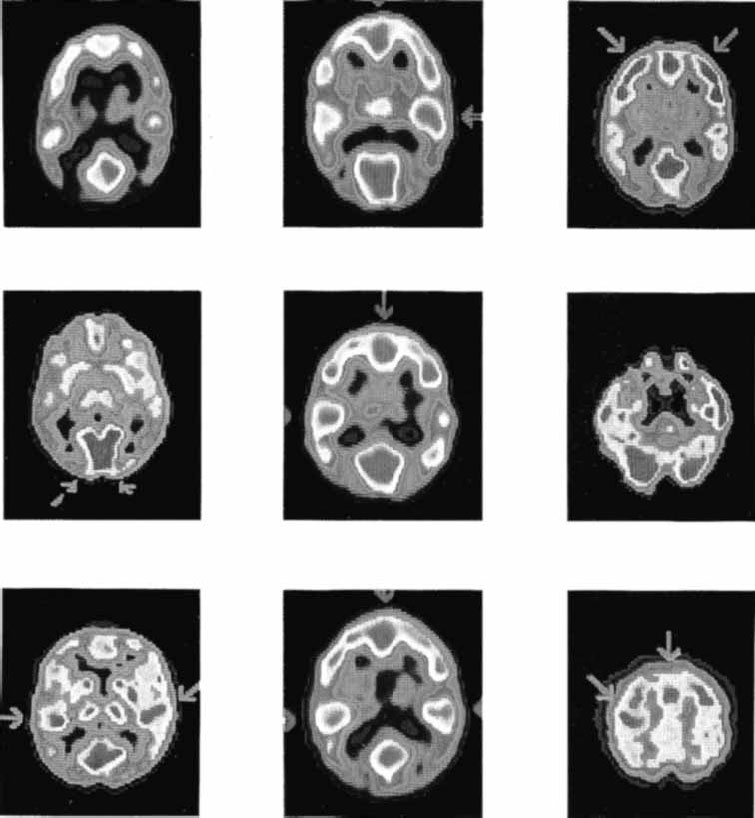

Время полураспада этих веществ составляет от 110 сек для фтора до 120 сек для кислорода. Метаболически активные участки мозга с большей интенсивностью поглощают 2-дезоксиглюкозу из крови, которая в отличие от обычной глюкозы не включается в метаболические процессы и только накапливается в мозге. Радиоактивные изотопы излучают позитроны, которые, встречая в мозге электроны, уничтожаются (аннигилируют), излучая 2 гамма-луча, направляющиеся в противоположные стороны. В специальной камере монтируются детекторы гамма-лучей, собранные в кольца. В камеру помещается голова испытуемого, радиоактивные молекулы 2-дезоксиглюкозы фиксируются сканером (Plum e. a., 1976) (рис. 2.16). Полученные данные обрабатываются компьютером, и на основе результатов воссоздается картина метаболически активных участков мозга.

Рис. 2.16. Результаты ПЭТ сканирования мозга здорового человека в различных экспериментальных ситуациях (Phelps, Mazziotta, 1985).

Особенностью ПЭТ является то, что она позволяет снимать «динамические» картины функционирования мозга, решающего ту или иную задачу или пребывающего во сне. Использование кислорода позволяет получать характеристики регионального кровотока, объема крови, потребления кислорода. Однако и кислород, и глюкоза попадают в мозг с током крови, изменение которого происходит иногда в течение нескольких минут. Поэтому быстропротекающие процессы пока этим методом фиксировать не удается.